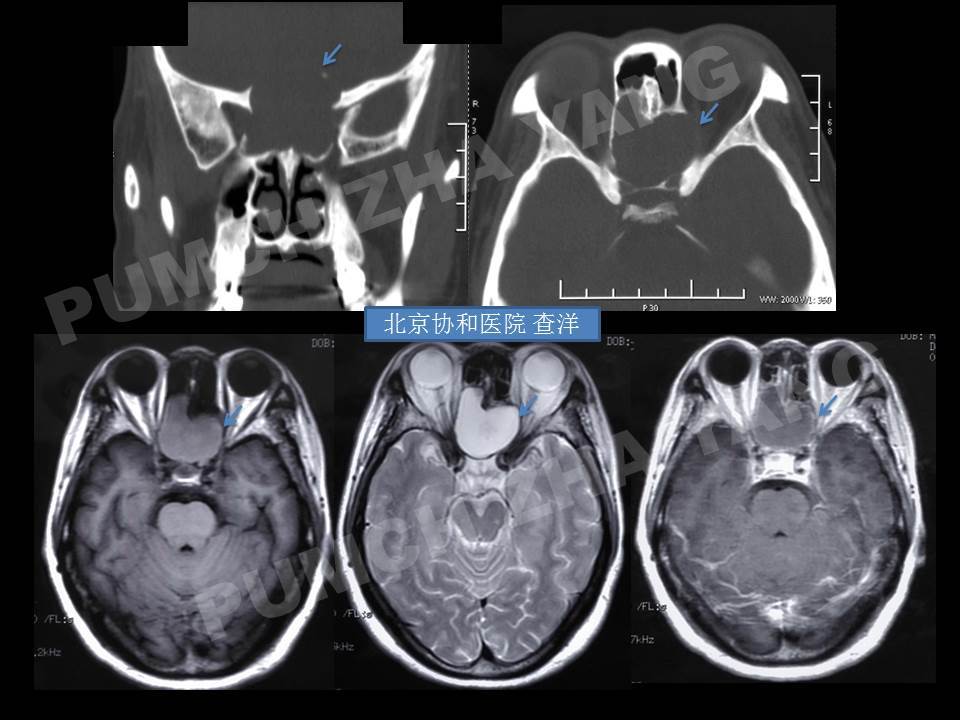

流泪来诊,找到了秦教授,副鼻窦部ct及mri增强扫描示筛窦粘液囊肿,鼻窦